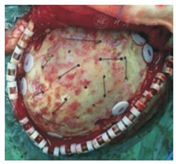

25例患者均在初次术后3~6个月给予颅骨回植,采用气管插管、静脉复合麻醉。沿原切口进入,自帽状腱膜下分离皮瓣,仔细将颞肌与硬脑膜分离,若有硬脑膜破损处则用骨膜或颞肌筋膜修补,显露前、上、后及颅底部分骨窗缘。用磨钻磨除骨窗周缘陈旧增生的骨痂,使骨面新鲜。把骨瓣植入原骨窗,四周用颅骨锁固定(图2)。术中电凝止血时需辅助生理盐水降温,减轻对大脑皮层的热传导。悬吊硬脑膜或假膜于骨瓣钻孔处,以减少骨窗下死腔及硬膜外血肿形成可能。头皮下置负压引流管1根,逐层缝合头皮并固定引流管。

液氮保存后的自体颅骨外观如新鲜骨瓣(图1)。钻孔所得患者骨屑细菌培养均为阴性,病理检查可见成骨细胞及骨小梁(图3)。